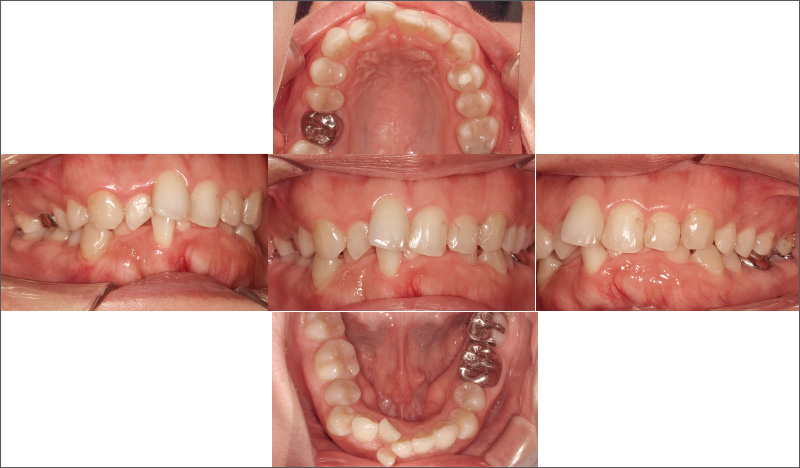

症例3-1 前歯の叢生と左右非対称であることを主訴に来院した30代女性。「iGo」による前歯部矯正治療に加えて、₅ ₅を立ち上げて、咬合再構成を行うことを提案した。 -

安定した口腔内を保つ30代女性。前歯の叢生と左右非対称であることが気になり、「iGo」での治療を希望。₅ ₅が舌側傾斜する鞍状歯列弓で、₆₅ ₅₆の咬頭嵌合位での咬合が確立されておらず、将来的に咬合が理由で前歯にトラブルが起こる可能性があることから、咬合再構成を提案しました。歯科における一般開業医の役割は、患者さんの口腔内が安定し、10年後、20年後も歯を失わずにいられる方法を考えることです。主訴だけでなく、口腔内の長期安定のため咬合までしっかりと診て適切なコンサルテーションを行い、治療につなげていくことが重要です。